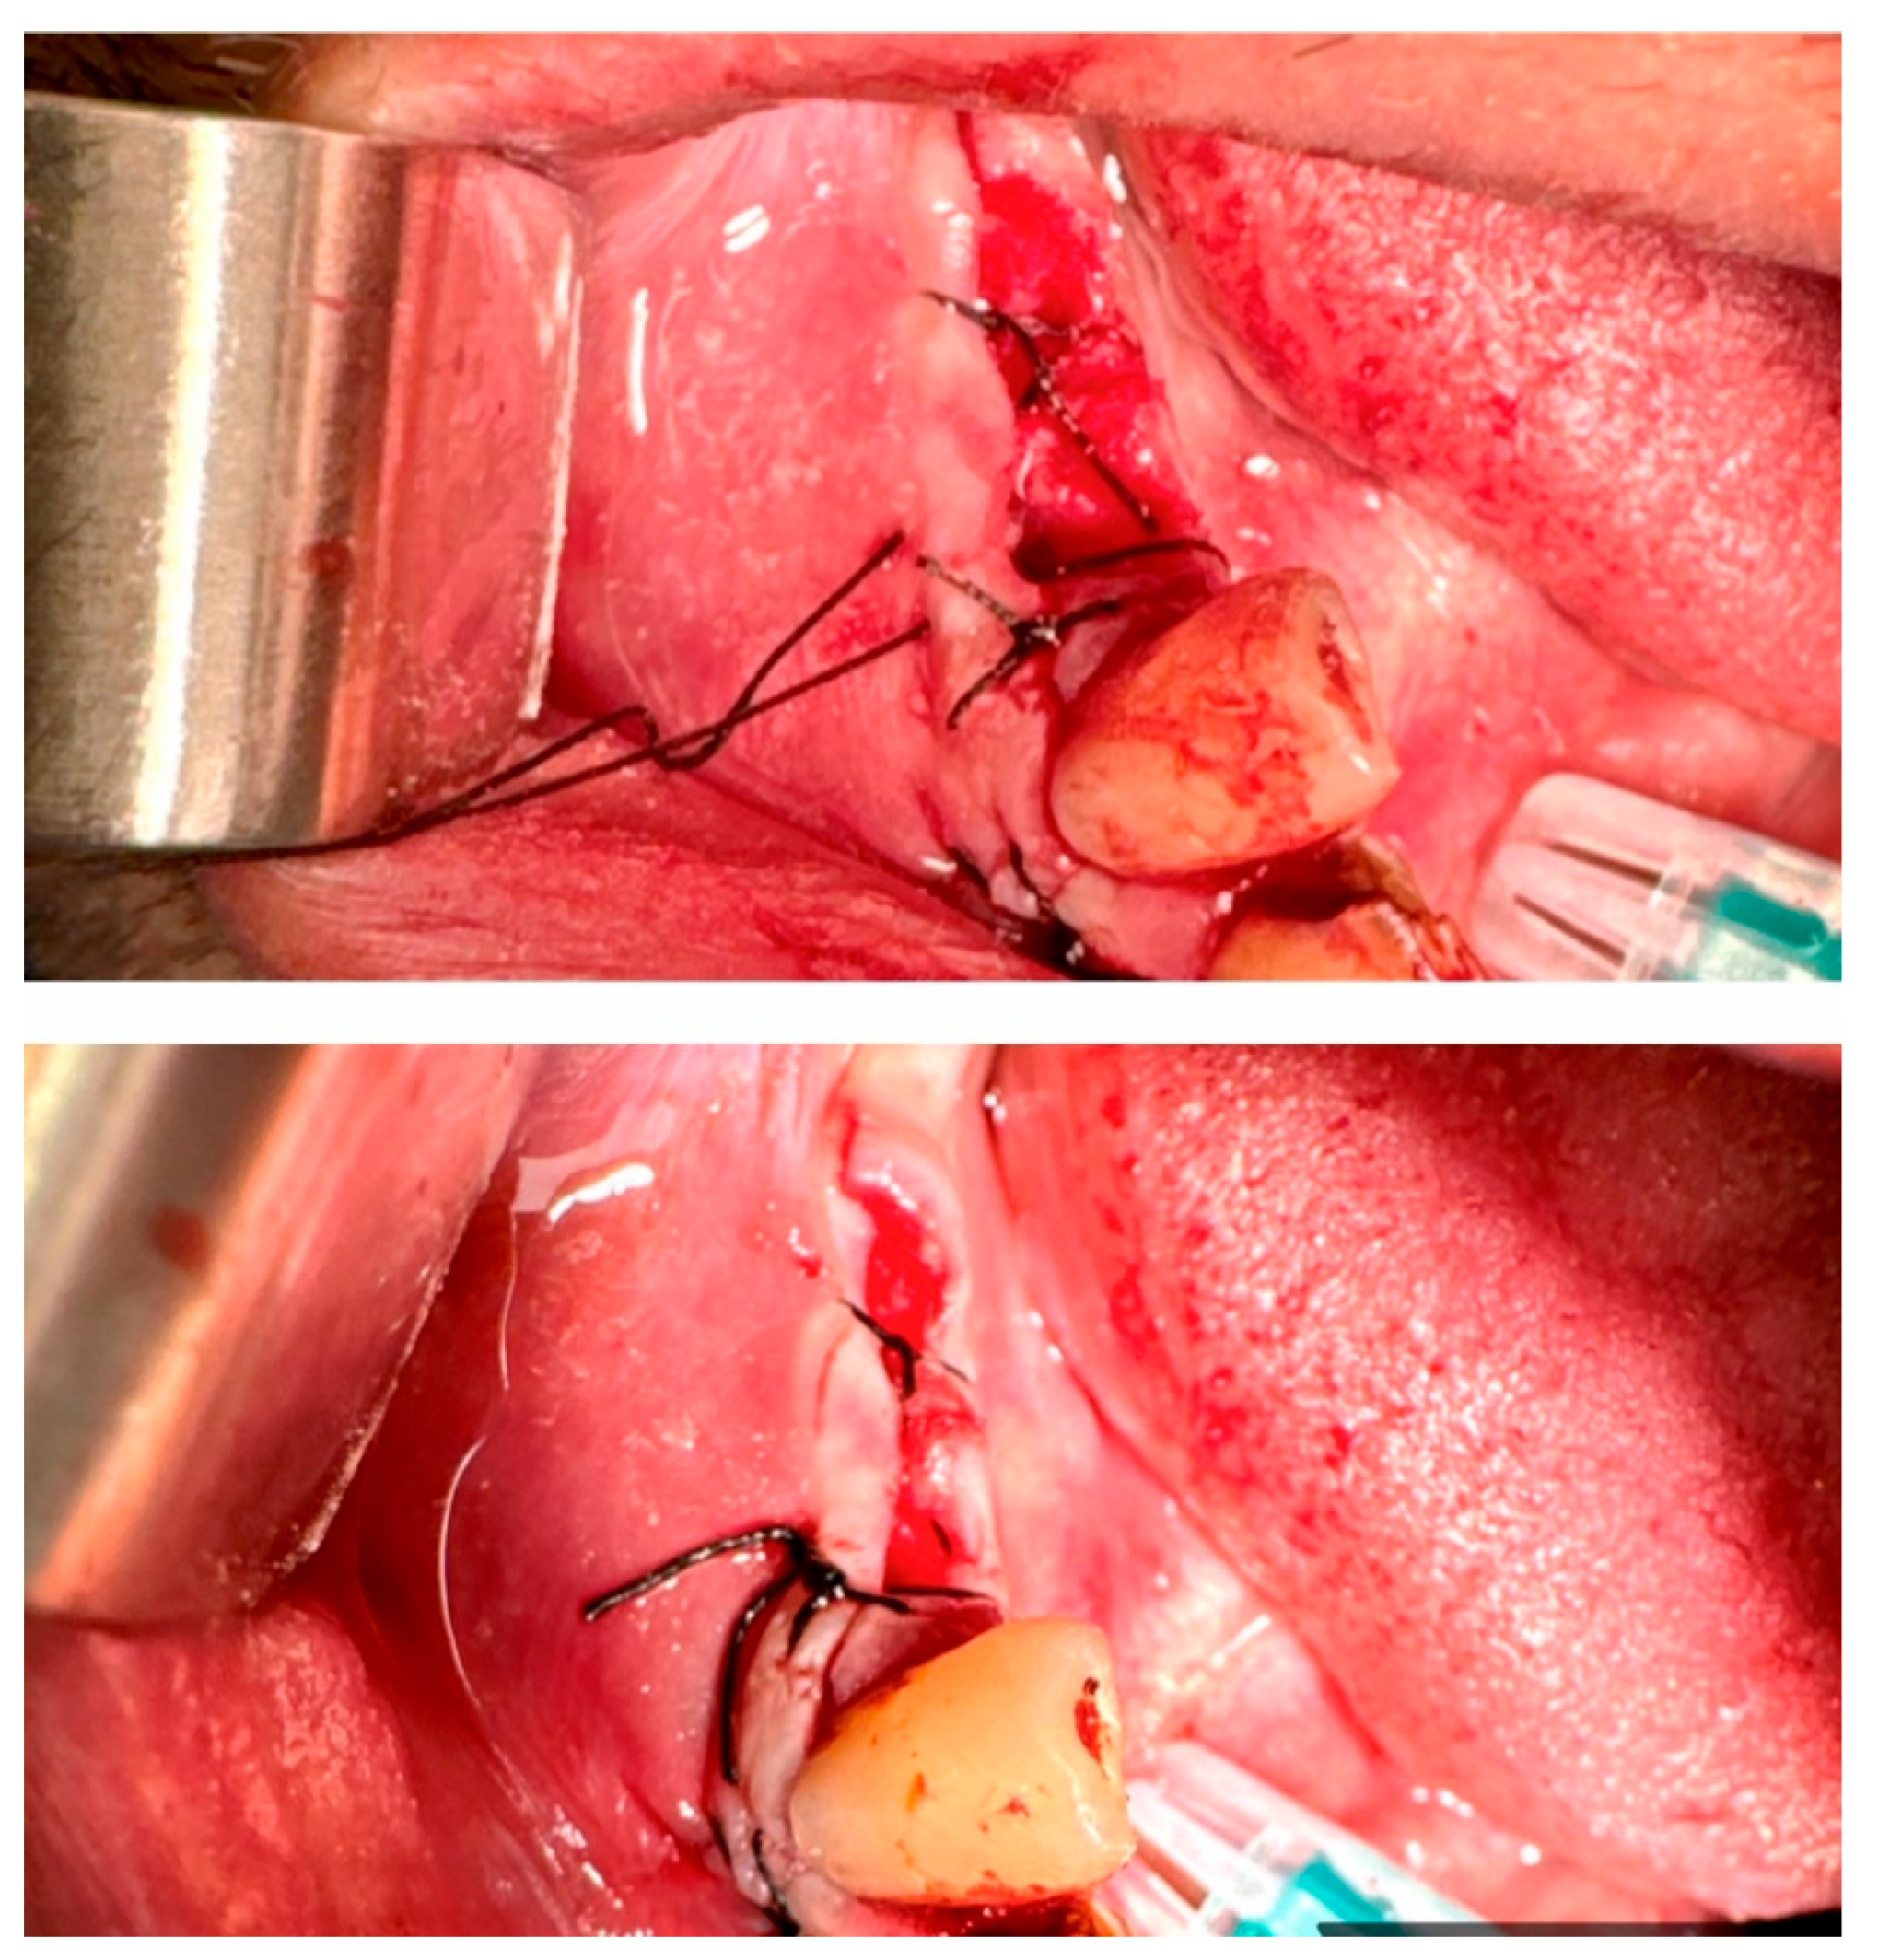

17. Surgical Suturing (Sutura Chirurgica)

- Single Throw Knot (One-Loop Knot, Figure 28)

- Square Knot (Simple Knot, Granny Knot, Figure 28):

- Surgeon's Knot (Two-Handed Knot, Double Throw Knot, Figure 28):